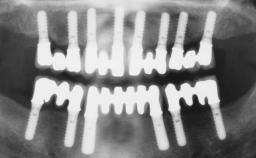

A 56-year-old female patient was referred to the clinic because of retention problems with her mandibular denture. She had been completely edentulous for more than 33 years and wore her sixth set of complete conventional dentures, which had been delivered 5 years previously. An oral surgeon had performed a vestibuloplasty in the interforaminal region of the mandible with a piece of skin tissue 12 years earlier. The panoramic radiograph and lateral cephalometric radiograph exhibited the hypotrophy of the inferior alveolar process. The mandible was a Cawood class VI,and the height of the mandible in the interforaminal zone was 15 mm.

# of Implants 2

Modality 2 interforaminal implants